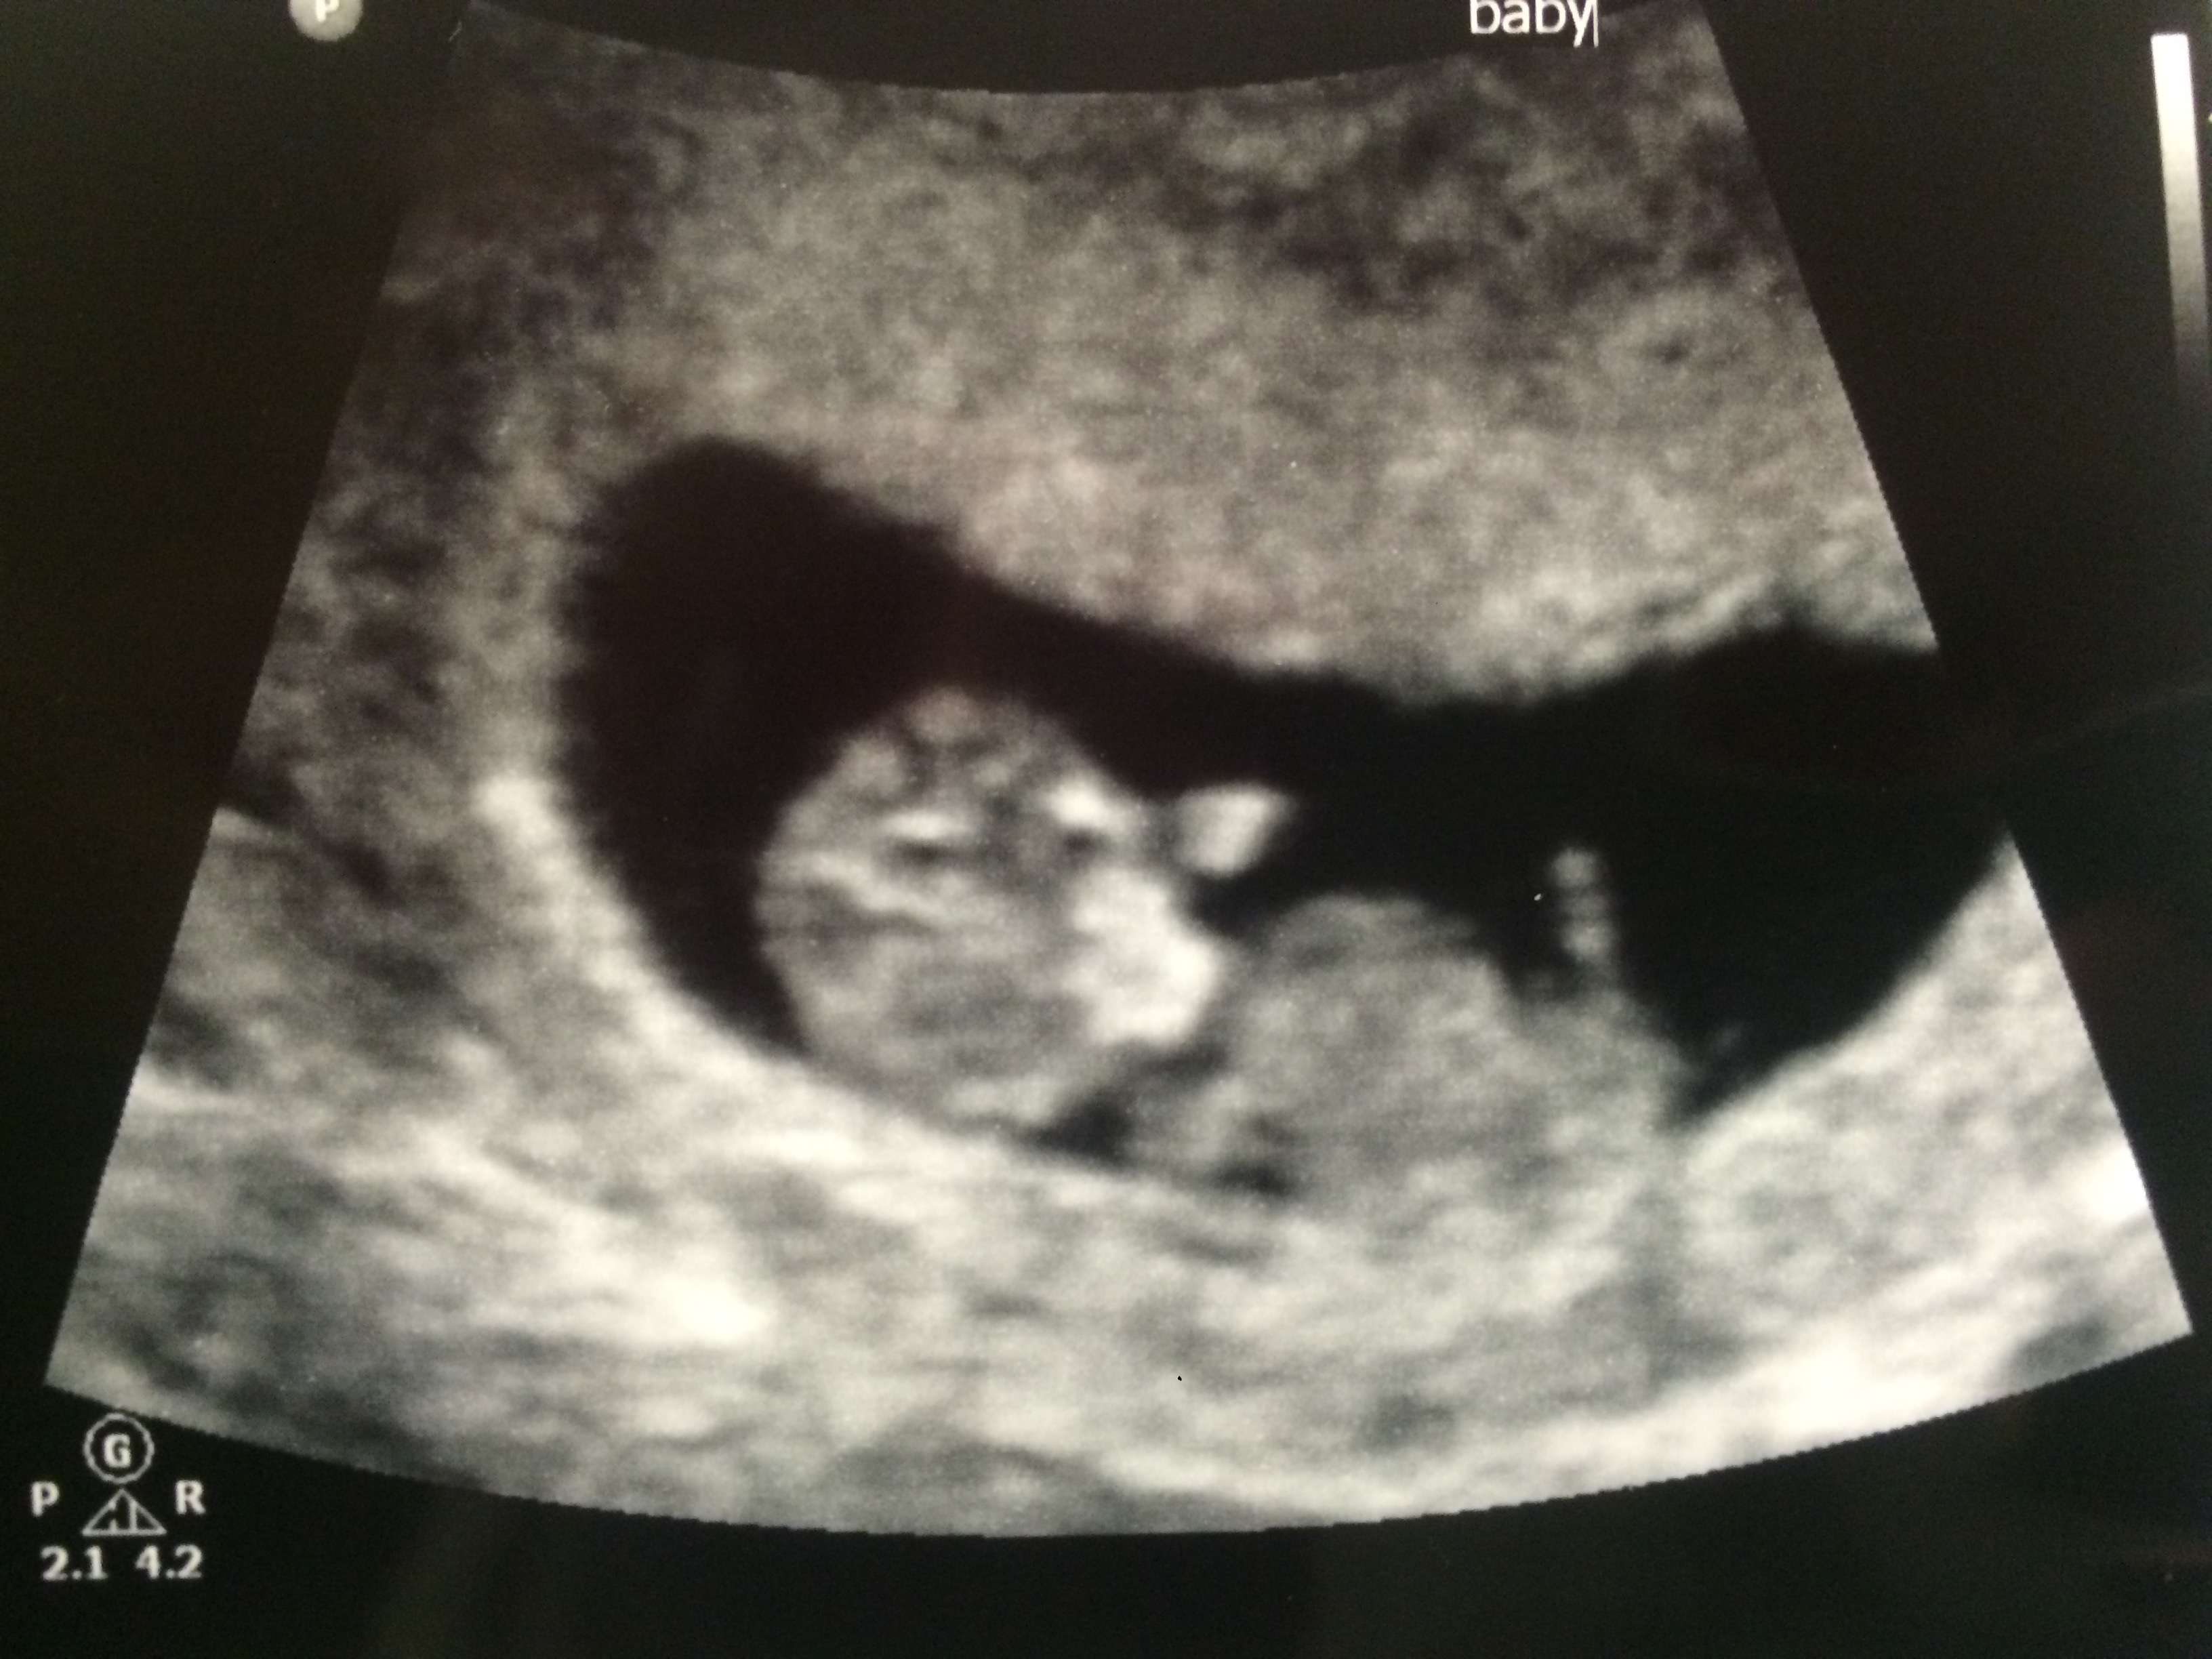

FTM! So excited to see how much my little gummy bear has grown in two weeks! 1st pic is at 6w5d, HR 147, and just a little blob with a flickering heart. 2nd & 3rd pics are at 8w5d, HR 176, and looked so much like a tiny baby with bitty arms and legs. Doc says baby is healthy and quite a dancer, it was moving and waiving all over the place. What a blessed moment to see!